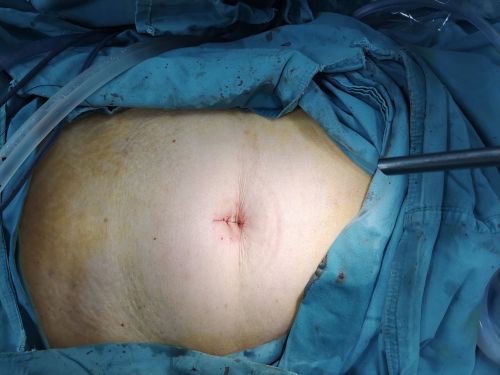

妇科黄薇主任团队为老人施行单孔腹腔镜下双附件切除手术。

在肚脐上打一个小孔,就完成全部手术操作。

手术结束,肚子上完全看不到手术切口。

术前高高隆起的肚子术后变得平坦。

经过充分讨论并做好充足的术前准备后,1112日,妇科黄薇主任团队在麻醉科、手术室的配合下,秉持无瘤操作原则,为老人施行单孔腹腔镜手术。在她肚脐上打一个小孔,缓慢引流出约4000毫升清亮的囊液。术中发现,左侧巨大的卵巢肿瘤与肠管致密大片粘连;精细分离后,顺利切除缩小的卵巢肿瘤和双侧附件,快速病检证实为“双侧卵巢浆液性囊腺瘤”。